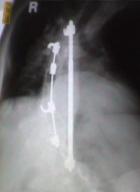

Harrington rods

X-ray after rods were

placed in my back

“The most common surgical procedure for scoliosis is posterior spinal fusion and

instrumentation... the insertion of metal rods, hooks, and screws to hold the curve from

moving for the 3 to 12 months that it takes for the fusion to become solid... "

During surgery, two Harrington rods were attached to vertebrae in my back

to immobilize the curving area of my spine.